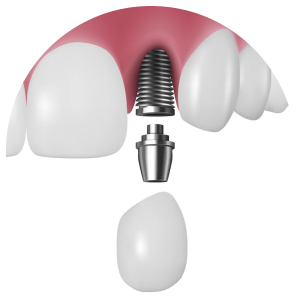

これは、虫歯や歯周病などで抜歯が必要になった際、その当日にインプラントを埋め込む方法です。従来であれば、抜歯後に歯ぐきや骨の治癒を数ヶ月待ったうえで次のステップへ進んでいましたが、この方法を用いることで、治療期間を短縮できるほか、手術の回数も抑えられます。